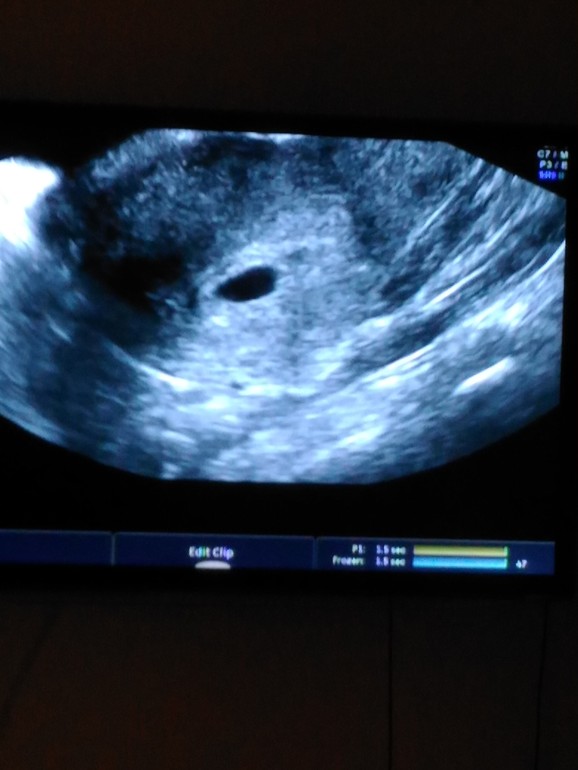

Первое УЗИ))

УЗИ, КТГ, доплерВчера сходила на первое узи, чтобы убедится, что все у нас хорошо)

1 плодное яйцо в матке. Срок 5 недель и 2 дня. Сделала фото) все у нас хорошо))